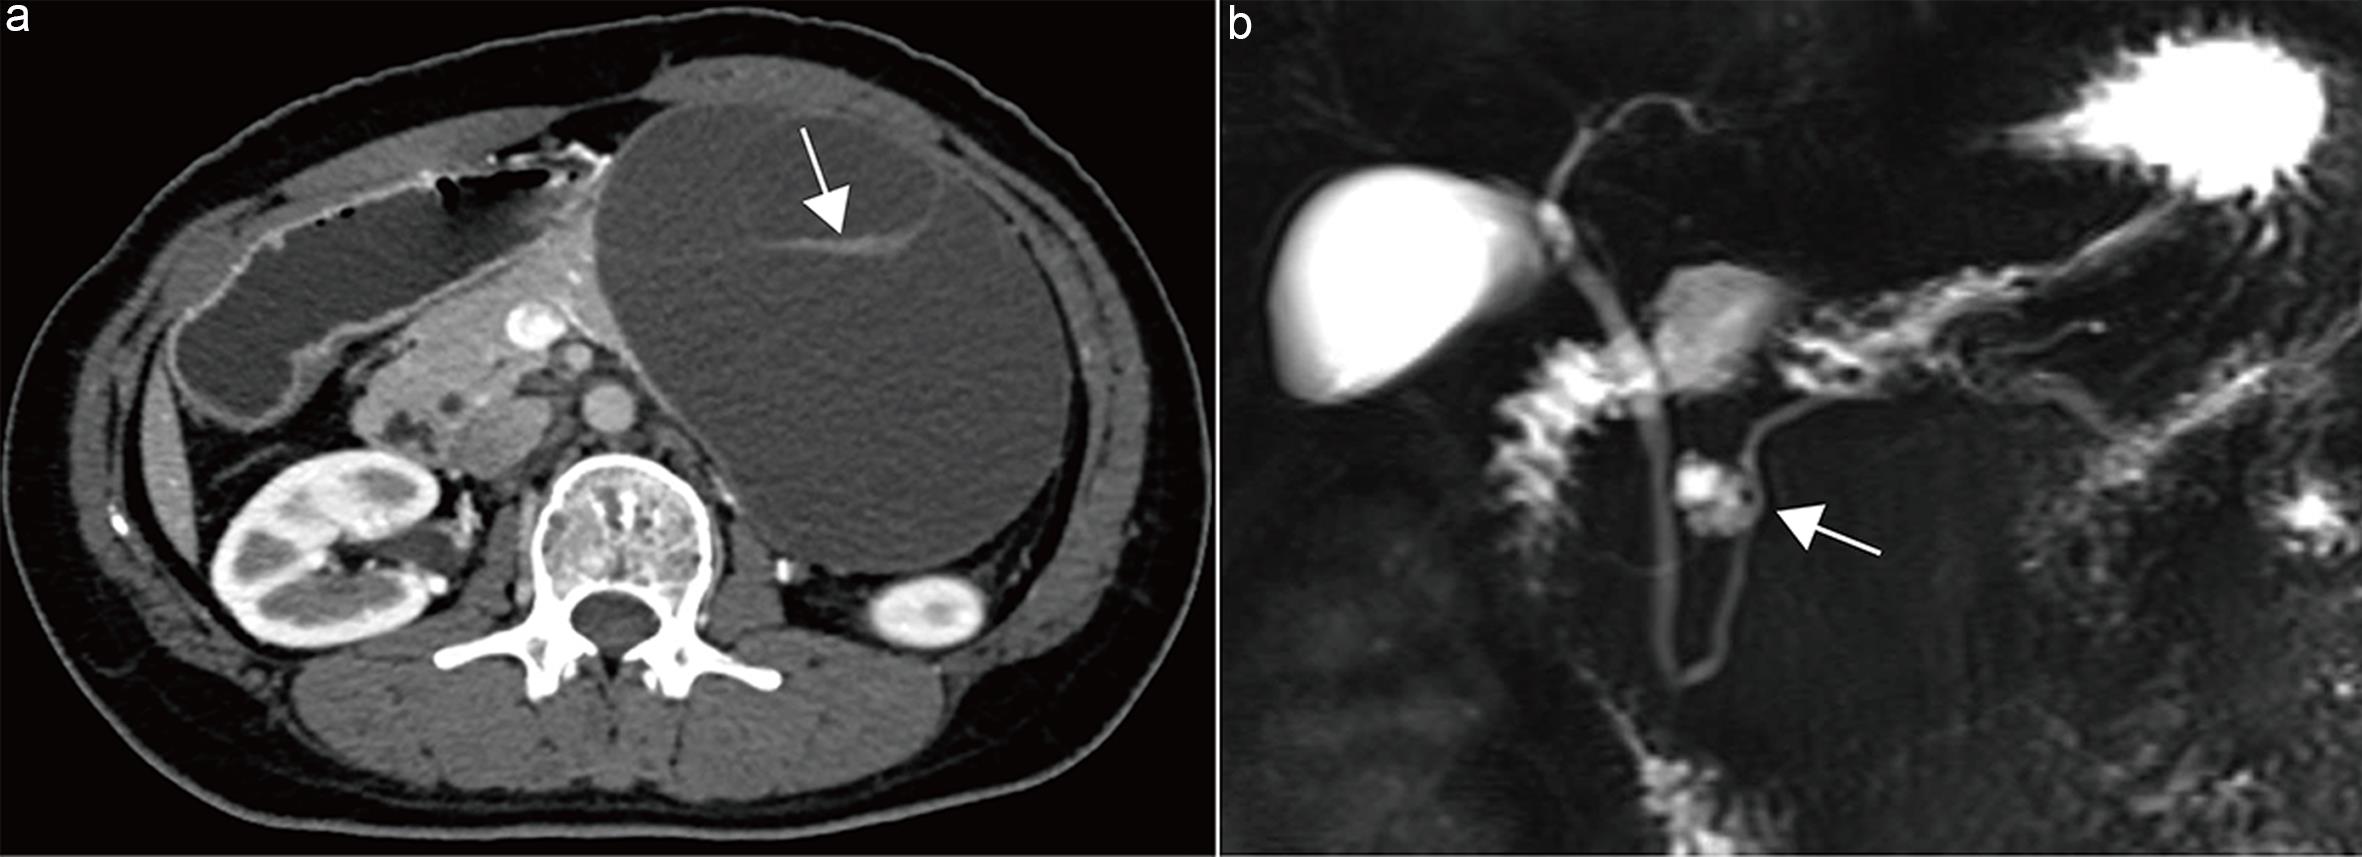

Therefore, this guideline recommends that imaging reports explicitly state whether main pancreatic duct obstruction is present; if so, the location and morphology (stricture versus cutoff) should be clearly described (Fig. 6).

Main-duct intraductal papillary mucinous neoplasm (MD-IPMN).

Fig. 6  Main-duct intraductal papillary mucinous neoplasm (MD-IPMN).

Axial contrast-enhanced pancreatic parenchymal phase computed tomography (CT) image shows an abrupt cutoff of the main pancreatic duct in the pancreatic body (arrow).